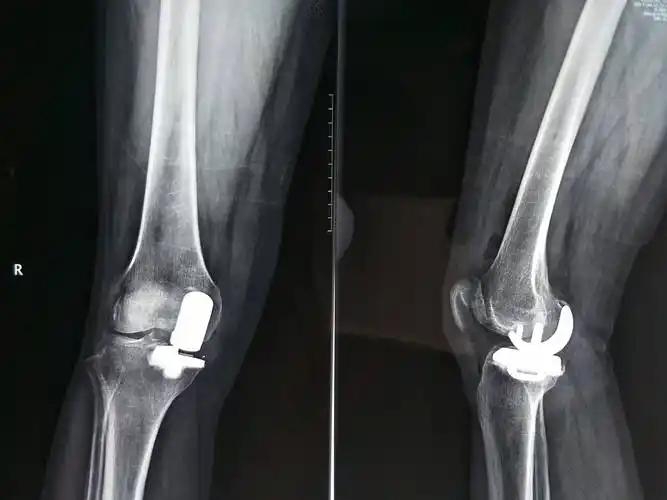

第四,選擇科學治療手段。如果膝蓋疼痛輕微,優先通過生活調理和康復訓練改善;若癥狀明顯,可在醫生評估后進行關節沖洗+玻璃酸鈉+激素注射,但要嚴格遵守“低頻次、小劑量”原則,避免嚴重副作用;當病情發展到晚期,軟骨嚴重磨損、關節畸形時,需及時咨詢骨科醫生,評估是否需要關節置換手術治療。

膝關節置換術后